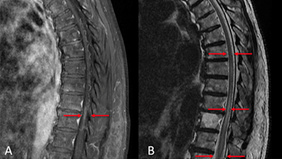

Endovascular Treatment Of Carotid Body Tumor With Embospheres

By Smit SHAH

Published on February 24, 2026